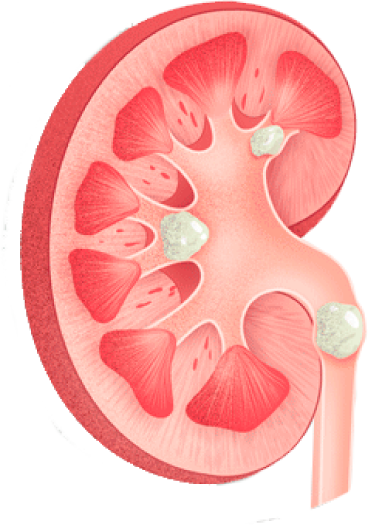

“Gracias a la prevención, el doctor pudo identificar una infección en etapa temprana”

- Lourdes Campos Uribe